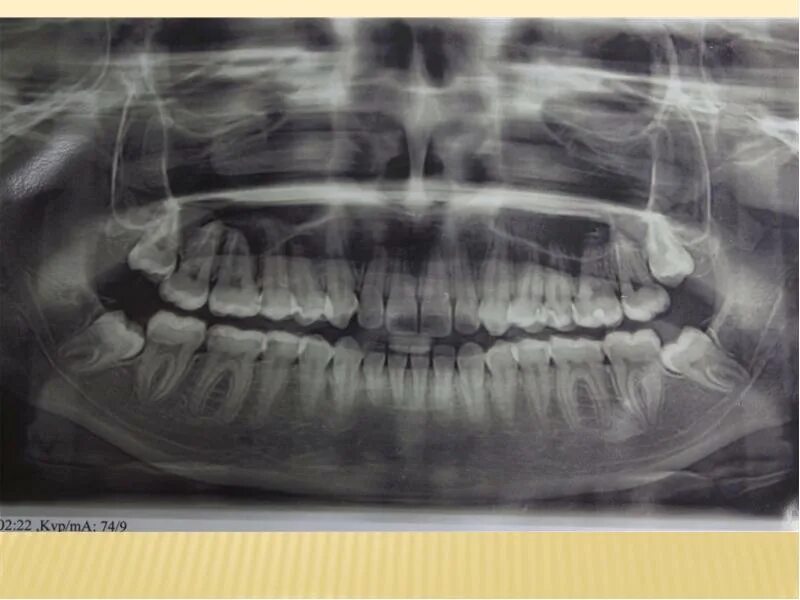

Зуб дистопирован